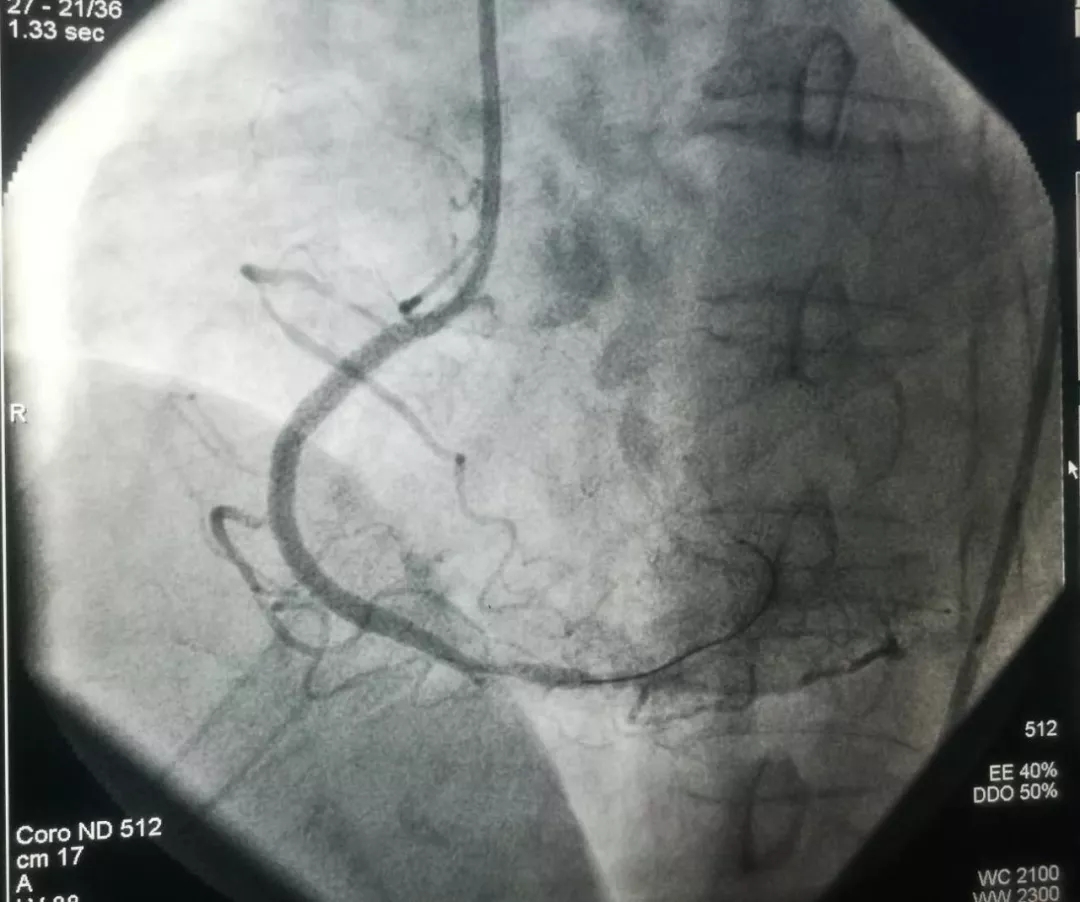

记文理病区开展首例冠状动脉造影术、冠状动脉支架植入术